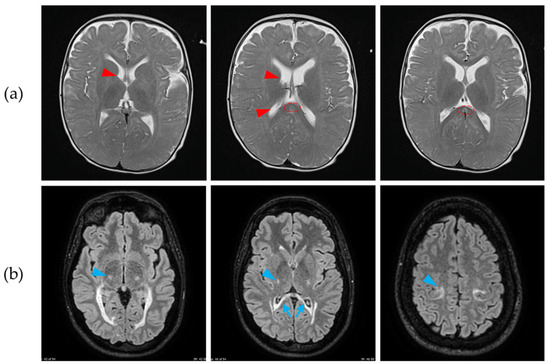

Longitudinal Changes in Brain Network Metrics and Their Correlations with Spinal Cord Diffusion Tensor Imaging Parameters Following Spinal Cord Injury and Regenerative Therapy

Objectives: Spinal cord injury (SCI) disrupts the microstructure of the spinal cord, triggers reorganization of the brain network, and causes motor deficits. However, the temporal dynamics and interrelationships of these alterations remain unclear. Methods: Eight monkeys underwent spinal cord hemisection and were randomly assigned to either the SCI-only group or the treatment group that received neurotrophin-3-chitosan implants. Longitudinal brain structural/resting-state magnetic resonance imaging and spinal cord diffusion tensor imaging (DTI) were conducted. Concurrently, hindlimb motor function was assessed. The brain network topology was characterized through graph theory. The generalized additive mixed model (GAMM) was employed to analyze the longitudinal trajectories of network metrics, while the linear mixed-effects model (LMM) was used to evaluate the moderating effect of treatment on correlations between network metrics and motor/DTI parameters. Results: The SCI-only group exhibited sustained functional network segregation, aberrant structural topology, and lower fractional anisotropy (FA). These findings collectively reflect chronic maladaptive plasticity. In the treatment group, the therapy not only enhanced white matter integrity, reflected by increased FA values, but also reduced the clustering coefficient (Cp) in brain structural network, indicating a shift away from maladaptive segregation. Critically, the LMMs further revealed that treatment moderated the pathological correlations between global efficiency (Eg), local efficiency, Cp, and locomotor parameters. Moreover, spinal FA exerted a significant main effect on Eg of brain functional networks. Conclusions: These findings suggest that treatment-induced brain reorganization underlies motor function following SCI, and progressive brain reorganization correlates with changes in spinal cord microstructure, revealing a systems-level mechanism of neural repair. Full article